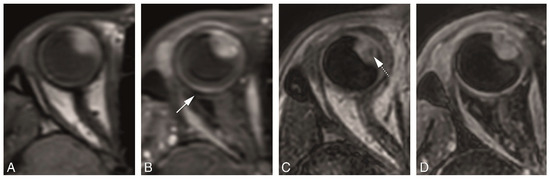

4.2. Anatomical MRI of Uveal Melanoma